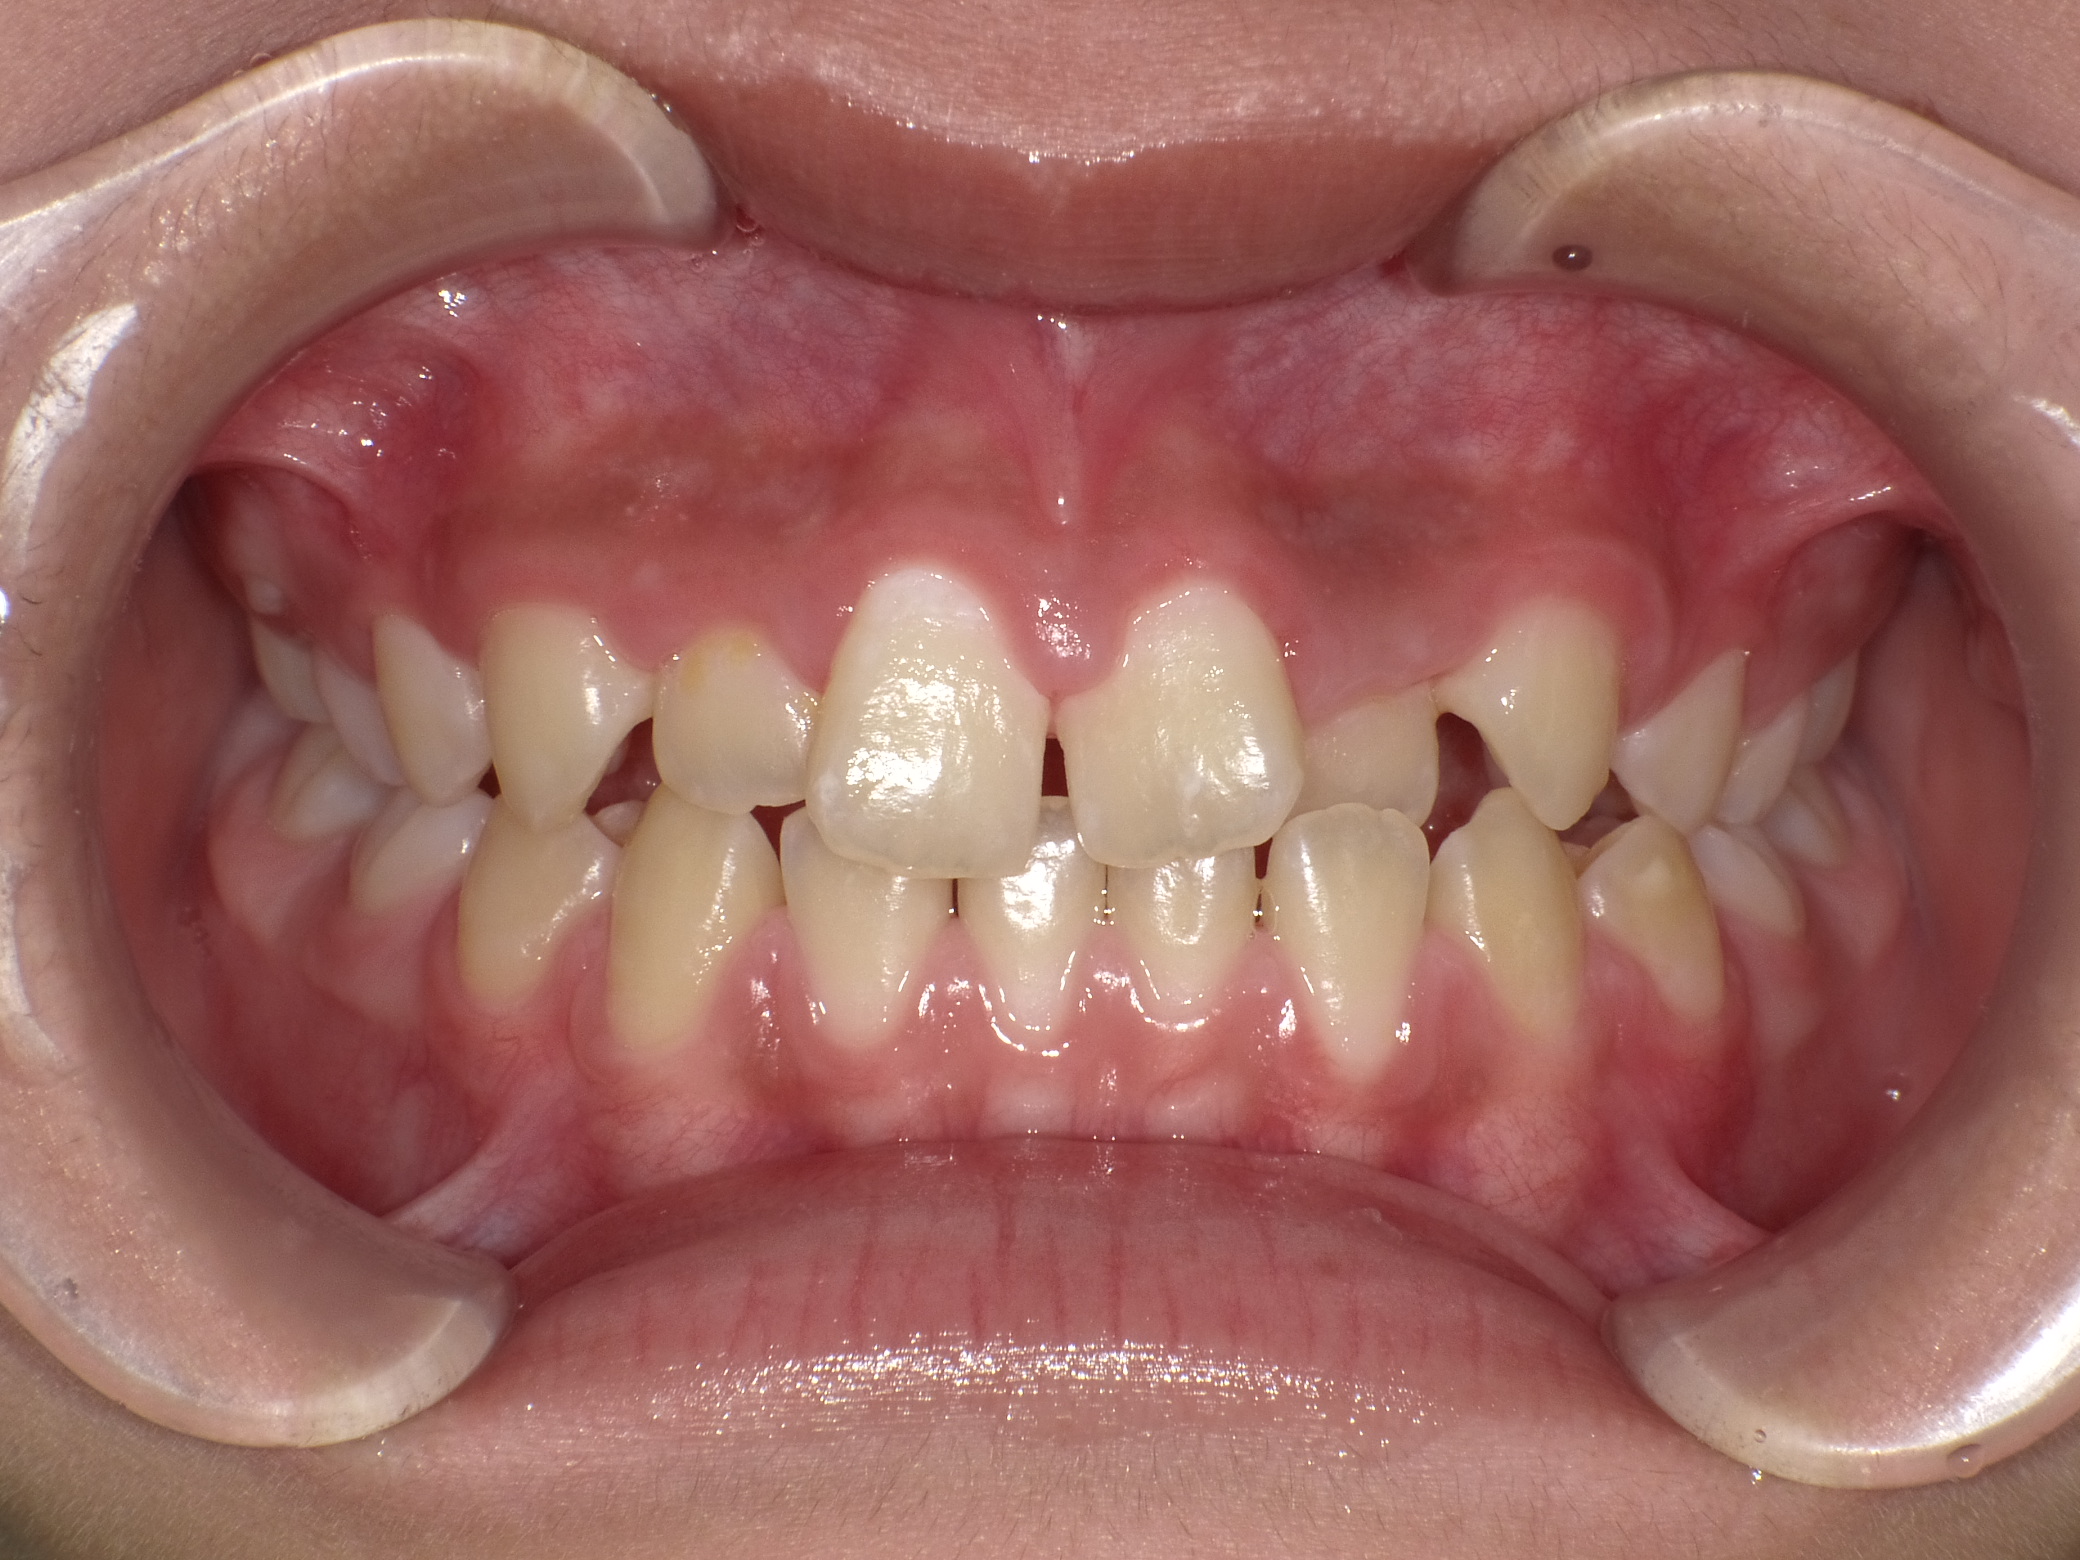

【小学生】マイオブレース矯正 受け口を改善 ①

小学生で開始

マイオブレース

受け口

1期治療のみで改善

Before

After

治療期間

1年11カ月年

治療開始

10歳

種類

マイオブレース矯正

使用装置

機能矯正装置

コメント

毎日装置の装着と MFT 口腔筋機能療法 に取り組んでくれたためスムーズに終わりました。

上顎前歯の並びをもう少し別の装置で改善することも提案しましたが、本人、保護者の方ともに

今の歯並びで満足しているということだったのでこれで終了しています。

MFTを頑張ってくれたため、お口の筋肉バランスもよく、後戻りもしていません。